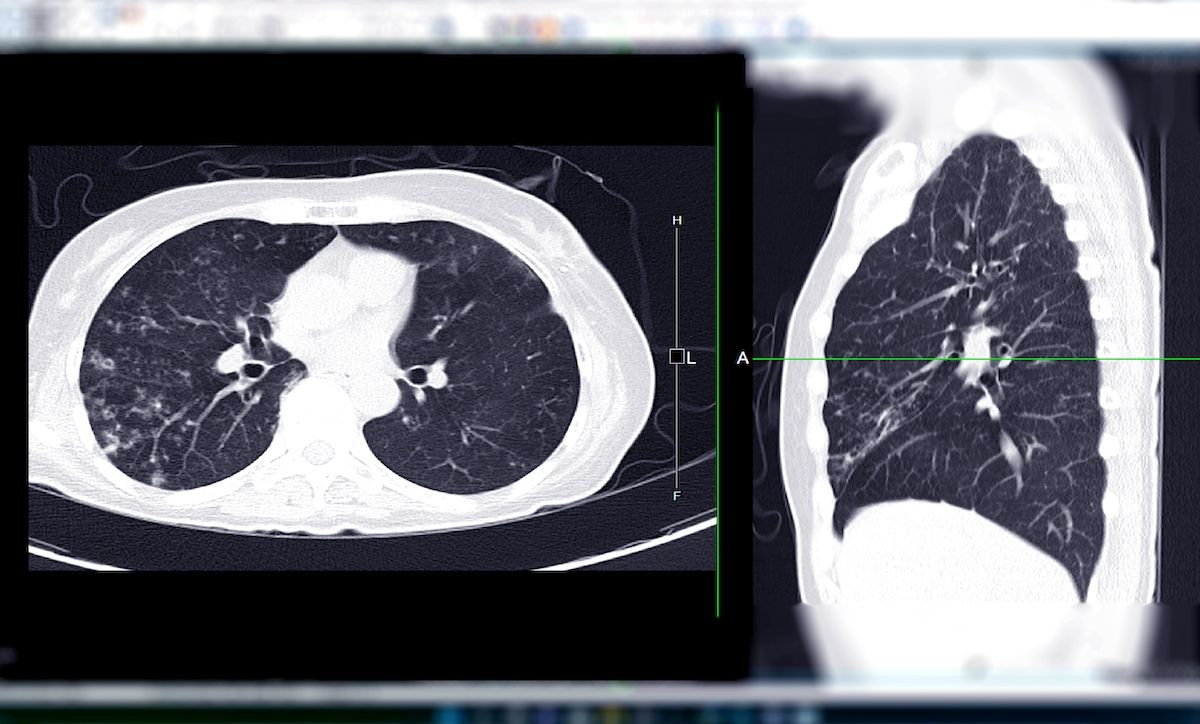

Despite updated guidance in 2021, overall screening rates for lung cancer remain low | Image Credit: samunella - stock.adobe.com